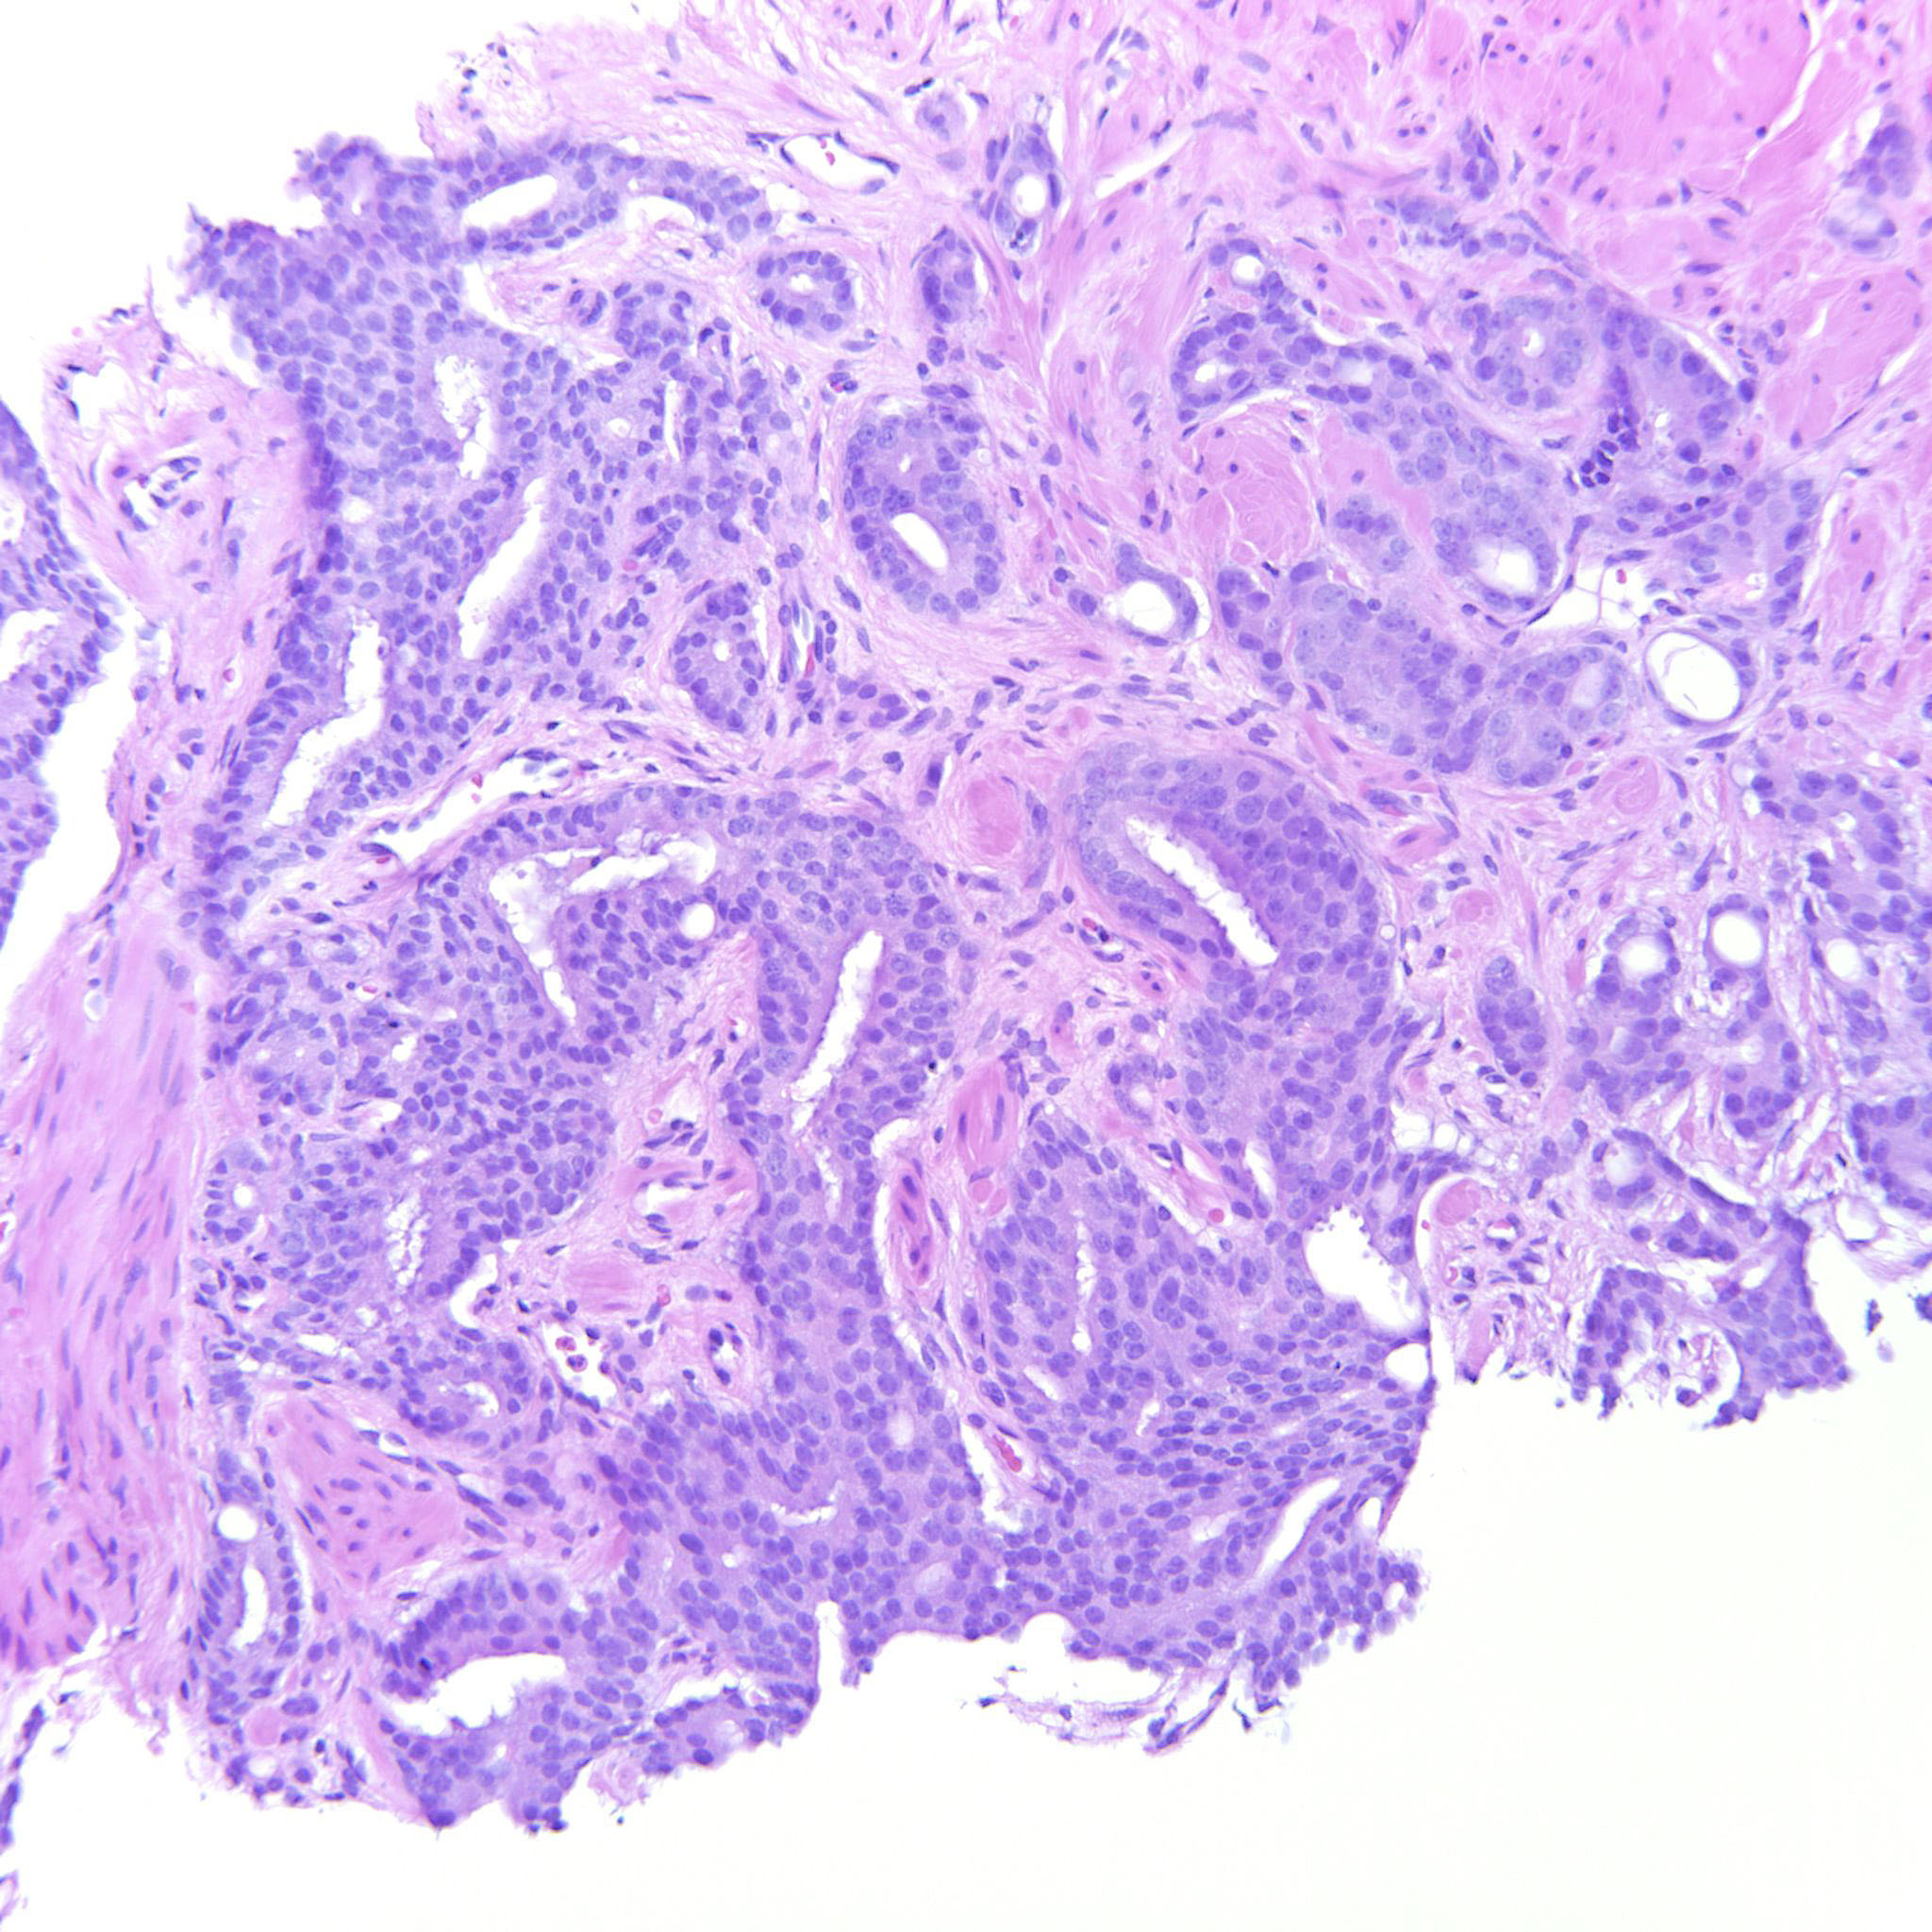

Prostate cancer grading

Case ID: 306